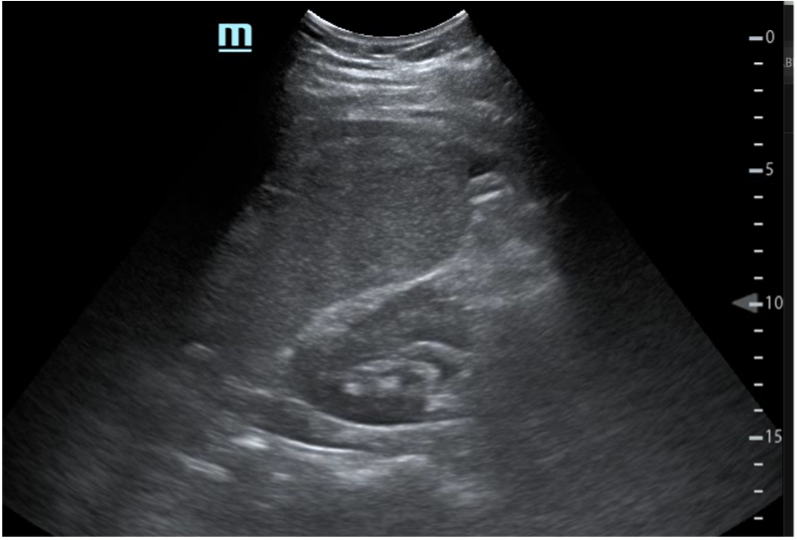

EF: Mal estado general, palidez mucocutánea, sudoración profusa. Intolerancia al decúbito supino con postura antiálgica. Abdomen: doloroso a la palpación difusa con defensa abdominal generalizada. Se realiza ecografía clínica a pie de cama objetivando líquido libre abdominal.

Hematoma subcapsular espontáneo del bazo.

Paciente con cuadro de abdomen agudo ante hallazgos en ecografía clínica y anemización se solicita TAC abdominal para completar estudio. Ante diagnóstico de hematoma subcapsular esplénico y hemoperitoneo sin sangrado activo, ingresa para control del dolor y seguimiento clínico sin necesidad de intervención quirúrgica. Se solicitan serologías resultando negativas.

En este caso se pone de manifiesto la gran utilidad de la ecografía clínica a pie de cama para el enfoque diagnóstico y manejo de un paciente en urgencias.